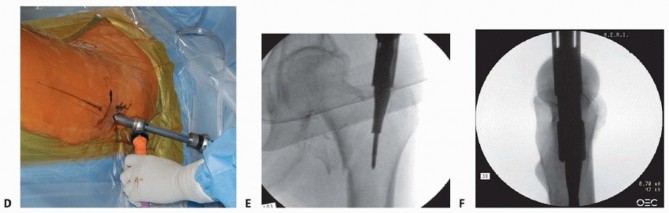

** Fracture Reduction Reduction of the fracture is tantamount to success. My preferred technique for the proximal femur involves a four-step technique. After attachment to the foot positioner or skeletal traction with the perineal post attached, posterior sag is corrected at the fracture with a force directed from posterior to anterior and maintained. The leg is flexed through the foot holder 20 to 30 degrees from neutral for intertrochanteric personality fractures and 30 to 40 degrees for subtrochanteric personality fractures, maintaining the posterior to anterior reduction force at the hip ( TECH FIG 1A). Traction is applied to restore length in line with the body. No varus. The leg is rotated to align with the proximal fragment, 5 to 15 degrees of external rotation for most subtrochanteric personality fractures and intertrochanteric personality fractures may be externally rotated 10 degrees or placed in 15 degrees of internal rotation for as the variability of femoral neck anteversion is larger than previously recognized. 5

TECH FIG 1 • A. Reduction maneuver with force directed posterior to anterior at the fracture to align anterior cortices, flexion of distal fragment to match proximal fragment, and then longitudinal traction. B. Percutaneous Schanz pin as joystick in proximal fragment.

(continued)

Acceptable alignment is confirmed with the C-arm in both views. The surgeon ensures there is adequate room in the pelvic and abdominal areas for the insertion of the wires, reamers, and implants in relation to the fracture table. A 3 L bag of saline may elevate the pelvis high enough to allow room for the instrumentation. The reduction can then be fine-tuned with intramedullary instruments or by percutaneous joysticks or pushers ( TECH FIG 1B,C). If the reduction is not acceptable at this point, the surgeon should stop and reevaluate the position of the C-arm and the amount of traction (too little or too much). The surgeon should not start reaming the proximal femur until reduction control is demonstrated. If reduction cannot be obtained by joysticks and percutaneous bone hooks ( TECH FIG 1D), the surgeon should proceed to open reduction using the lower portion of a Watson-Jones-type approach to the hip (TECH FIG 1E-I). The surgeon should avoid dissecting the medial soft tissue envelope, where the vascularity is located. A single cerclage wire will be most helpful if there is a coronal split of the proximal fragment. Use of multiple cables or wires is avoided. The clamps and reduction tools are maintained as the implant is inserted. 393

TECH FIG 1 •

C. Percutaneous joystick eccentrically placed to allow passage of reducer. D. Percutaneous joystick and percutaneous bone hook. E. Open reduction Watson-Jones with two clamps for irreducible high-energy hip fracture. F. Open reduction AP radiograph. G. Open reduction lateral radiograph. H,I. AP and lateral radiographs showing final result. 1. ## Precision Portal Placement and Trajectory Control The rationale for the minimally invasive cephalomedullary surgical technique is based on three concepts to maximize bone and soft tissue conservation during nail implantation and to minimize the potential for malalignment 21: Precision portal placement Trajectory control Portal preservation A precise starting point is the first criterion in ensuring an accurate reduction of proximal fractures, whether the entry portal is a modified trochanteric entry portal or a piriformis portal as defined by the selected nail geometry ( TECH FIG 2A,B).